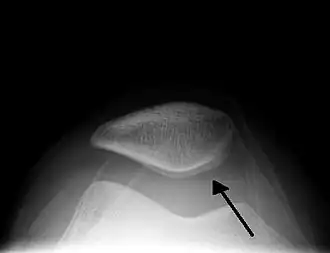

A traumatic right knee effusion. Note the swelling lateral to the kneecap as marked by the arrow.